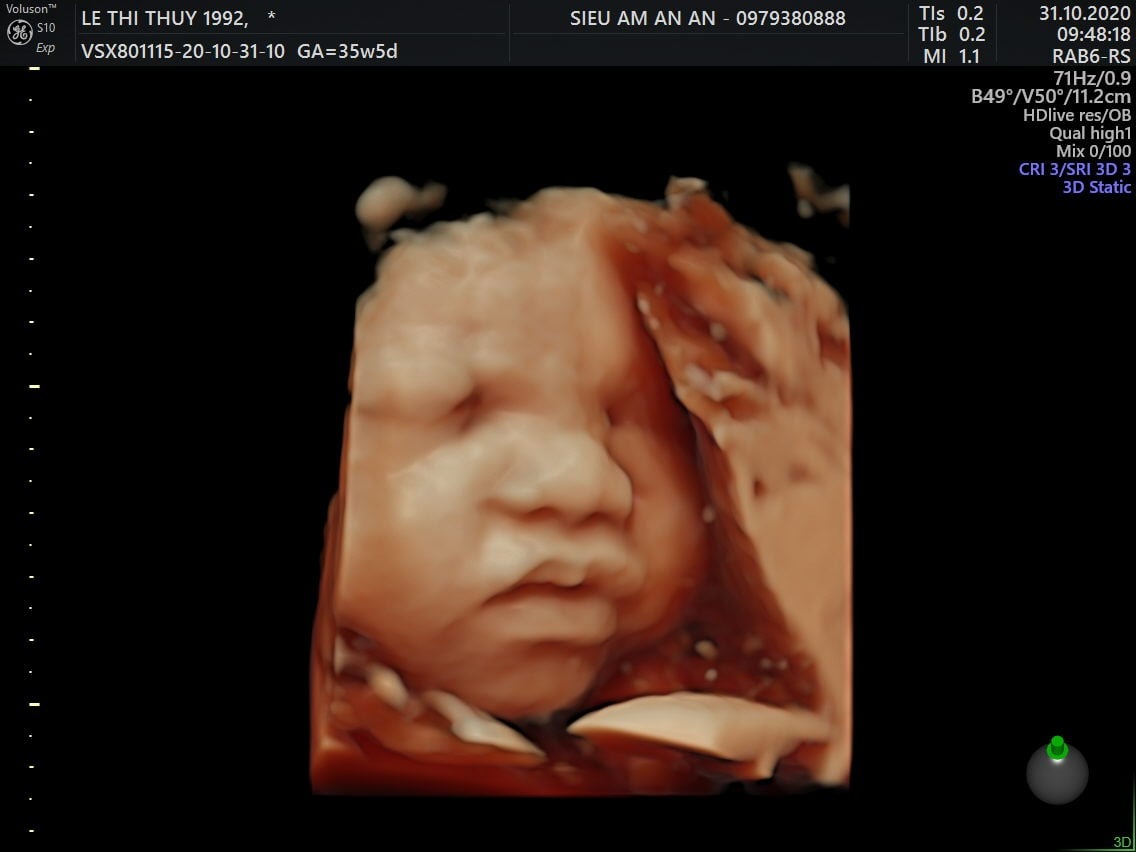

Thai nhi 36 tuần phát triển như thế nào? Ăn gì để con tăng cân, thai 36 tuần gò nhiều, thai 36 tuần nặng bao nhiêu là chuẩn? Qua siêu âm, mẹ có thể thấy hình ảnh một bé yêu mũm mĩm đáng yêu rất giống với em bé sơ sinh hoàn chỉnh. Điều này khiến nhiều mẹ thấy trái tim mình như tan chảy, bé yêu dường như đang đến rất gần rồi.

Chỉ còn khoảng 4 tuần nữa em bé sẽ chào đời, mẹ chắc chắn đang rất tò mò về sự phát triển của bé ở giai đoạn này. Khi mang thai tuần 36, mẹ dễ dàng theo dõi được hình thái của bé qua siêu âm. Các bộ phận chân, tay cử động nhẹ nhàng vô cùng đáng yêu. Hình ảnh mũm mĩm, mập mạp của bé thật sự khiến trái tim mẹ nào cũng phải tan chảy.

Ngược lại, nếu cơn gò nhiều đi kèm các triệu chứng ra máu, vỡ ối, rò rỉ ối, chóng mặt, ngất xỉu, đau liên tục, mẹ cần đến bệnh viện kiểm tra sức khỏe càng sớm càng tốt. Rất có thể mẹ đang đối mặt với hiện tượng sinh non. Qua hình ảnh thai nhi 36 tuần từ máy siêu âm, bác sĩ sẽ đưa ra chỉ định tối ưu nhất.